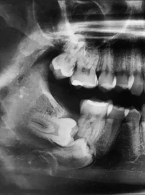

Powikłania związane z zatrzymaniem zębów stałych

Complication of permanent teeth impaction

Retentio dentis jako problem kliniczny w codziennej praktyce lekarza pedodonty. Opis przypadku

Retentio dentis as a clinical problem in daily practice of a pedodontist – a case report

Resorpcja korzeni zębów sąsiadujących z zatrzymanym kłem – przegląd piśmiennictwa. Część I

Resorption of the roots of teeth adjacent to the retained canine – review of the literature. Part I